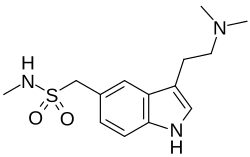

Migränetherapeutika

In der Therapie akuter Migräneattacken finden insbesondere 5-HT1B/1D-Rezeptoragonisten aus der Gruppe der Triptane wie beispielsweise Sumatriptan Anwendung. In der Migräneprophylaxe wurden hingegen, zumindest bis zum Siegeszug der Betablocker, Serotoninantagonisten wie Methysergid und Pizotifen genutzt.